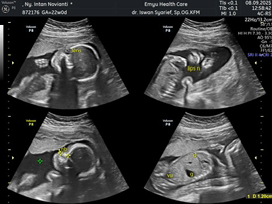

USG feto biasanya disarankan untuk risk pregnancy atau kehamilan beresiko tapi kalo bunda mau bagusnya itu diusia kehamilan 11-12 mggu untuk cek NIPT , 22-24 week untuk cek kelengkapan organ . USG nya sama tapi dokternya bersertifikasi khusus jadi penjelasannya dan report akan lebih detail.

Udh kk di usia 22w, tpi lebih disarankan pas 24w kata dokter fetonya

Aku udah bun, pas di uk 22w